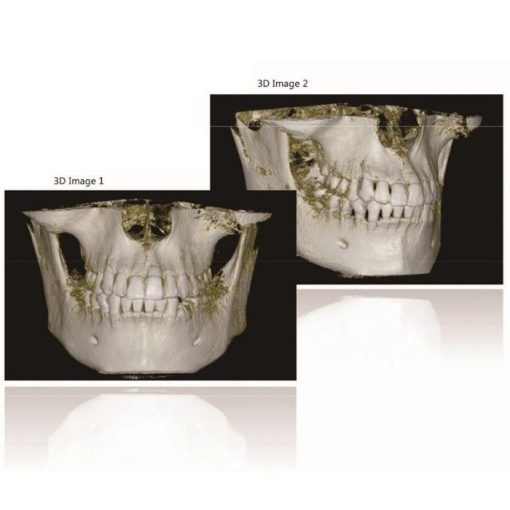

Presently is the most promising and revolutionary device of oral and skull imaging equipment. Its X-ray generator will move around the object for annular DR with low radiation, and after radiograph around the object for times, the jointed data will be reconstructed by the computer to get the 3D image. The application of CBCT has epoch-making meaning to oral health.

High Resolution Digital Image Chain

Digitalization mouth unit adopts unique HRBPR image reconstruction and WE image processing algorithm, and based on the super speed image reconstruction of CUDA technology, the NL-means image smoothing algorithm, and metal artifacts reduction algorithm etc, it provides the users 3D oral images with high resolution and high precision. Meanwhile, the applied pulse source technology can reduce the radiation level for patient and extend the lifetime of X-Ray tube.